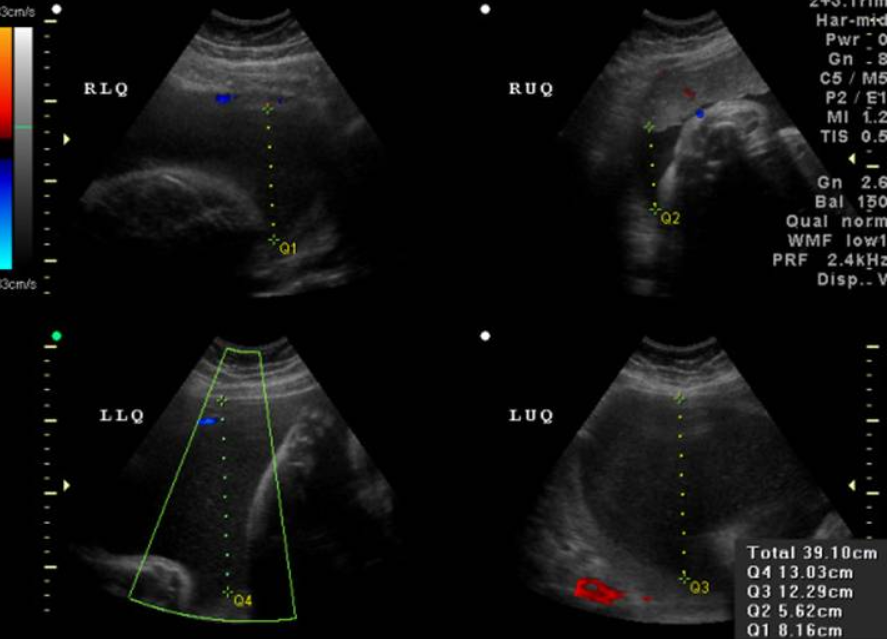

Chẩn đoán đa ối dựa vào các dấu hiệu lâm sàng tử cung căng, to hơn so với tuổi thai, khó sờ thấy các phần của thai. Để chẩn đoán xác định đa ối cần dựa vào siêu âm đo chỉ số ối AFI.

- Chỉ số ối AFI lớn hơn hoặc bằng 25cm: chẩn đoán đa ối

- Siêu âm giúp khảo sát một số nguyên nhân đa ối như: dị tật thai nhi, song thai, đa thai,..

- Ngoài ra siêu âm còn giúp chẩn đoán phân biệt đa ối với cổ trướng hay u buồng trứng.